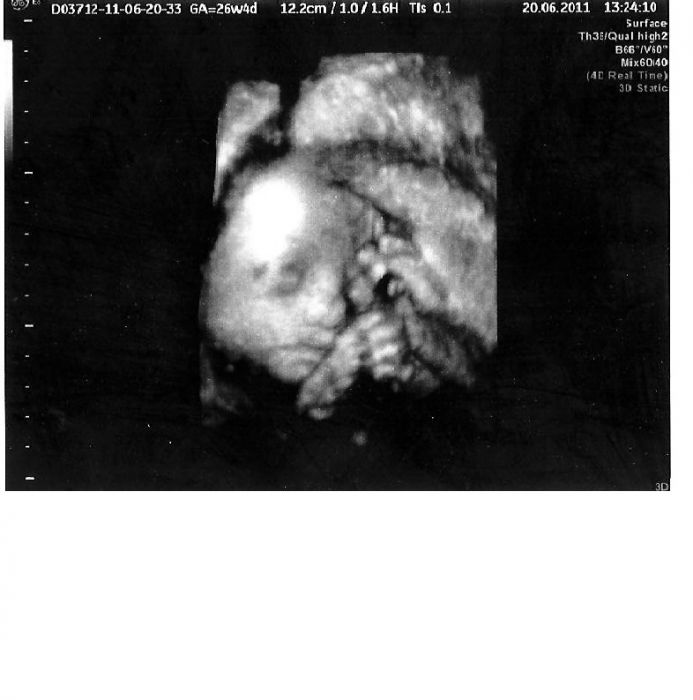

Pavli váš Matýsek má moc pěkný nosánek, ta moje prdelka bude mít po mě pršinos, snad nebude mít takový široký..ale to je mi úplně jedno, pro mě je to princezna...

Markett to se ještě neví jestli bude mít pěknej nosánek, je to brané trochu z boku. Ta tvoje je pěkně ze předu. Malá je krásná. Ale jak píšeš, nejkrásnější dítě budeme mít každá.